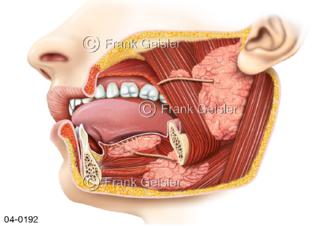

Bildergalerie Topografie Organe

Bilder zur topografischen Anatomie, die Lage der Organe und die Strukturen nach ihren räumlichen Lagebeziehungen zueinander, Übersicht der inneren Organe im Kopf und im Rumpf, Topografie der Organe im Brustraum (Thorax) und im Bauchraum (Abdomen)